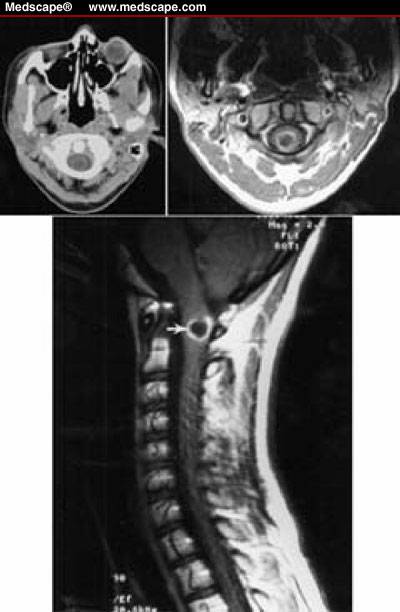

Các nang sán cũng có thể xảy ra khi nằm trong khoang não thất hoặc vùng dưới nhện, đôi khi chúng phát triển đủ lớn để hình thành nên các dấu chứng thần kinh, dấu màng não, não úng thủy, hoặc liệt các dây thần kinh sọ não - khiến cho thầy thuốc lâm sàng nhầm lẫn với các bệnh lý thần kinh khác (entrapment). Hiếm gặp hơn, các nang sán định vị trong cột tủy sống có thể gây ra triệu chứng đau rễ thần kinh hoặc dị cảm khó thể phân biệt với các bệnh lý tủy sống khác.

Sau khi thăm khám và điều tra bệnh sử, chụp cắt lớp vi tính có hoặc không có bơm thuốc cản quang đường tĩnh mạch là bước đầu tiên trong chẩn đoán các ca bệnh nghi ngờ ATSL thần kinh. CT não có hoặc không có thuốc cản quan sẽ cho thấy hình ảnh các tổn thương điển hình của ATSL đường kính nhỏ hơn 20mm và không có hình ảnh phản đứng giữa (no midline shift) là hình ảnh gợi ý cao cho thể ATTSL thần kinh (neurocysticercosis). Phần scolex, hoặc phần giác hút của ấu trùng cũng có thể nhìn thấy; đây là đặc trưng bệnh của ATSL thể thần kinh.

Hình 2. trên hình ảnh CT có nang của ATTSL thể thần kinh trong nhu mo não đặc | Hình 3. hình ảnh cộng hưởng từ cho thấy các nang của ATSL thể thần kinh trong nhu mô |

Số lượng, kích thước và vị trí có nang xuất hiện cũng như giai đoạn chu kỳ của nang sán, có thể xác định và có thể tác động đến việc quyết định điều trị. Các nang là các hình ảnh tổng thương dạng điểm có thể phát triển và tồn tại được, nang không bị thoái hóa. Các tổn thương dạng nang chỉ ra biến tính hoặc thoái hóa có một vài phản ứng viêm bao quanh. Cuối cùng, các nang hình thành calci hóa là một bằng chứng các nang đã tồn tại lâu có thể đã chết. Chăm sóc phải được tiến hành khi có thể còn nghĩ đến nhiều nguyên nhân khác (lao, bệnh ký sinh trùng khác, di căn từ nơi khác đến, hoặc ung thư nguyên phát của não hoặc hình ảnh abces não) khi một tổn thương tìm thấy trên phim chụp cắt lớp.

Hình ảnh trên phim chụp cộng hưởng từ cũng là công cụ hữu ích để chẩn đoán ATSL thể thần kinh và có thể tốt hơn cả chụp cắt lớp CT để phát hiện các thương tổn trong não tủy, trong cuống não, trong não thất. Việc áp dụng nó nên cân nhắc khi CT không chẩn đoán ra. CT và siêu âm là rất nhạy để phát hiện các tổn thương ATSL tại mắt và hệ cơ xương.